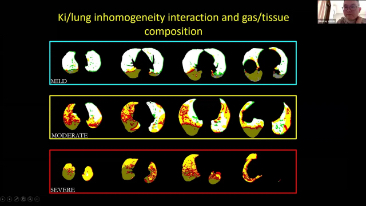

Das Beatmungsger?t im Einzelnen richtig einzustellen, ist bei der Behandlung von Patientinnen und Patienten mit Atemwegserkrankung von entscheidender Bedeutung . Da diese Einstellungen in Bezug auf s?mtliche Parameter von einem Arzt oder einer ?rztin vorgenommen werden, h?ngt ihre Angemessenheit direkt von deren Wissen und der Erfahrung, die sie mit solchen Einstellungen gesammelt haben, ab. In den letzten 20 Jahren hat sich der in der BeatmungsunterstĂŒtzung verfolgte Ansatz grundlegend weiterentwickelt. Ausgehend von den BedĂŒrfnissen der Praxis wurden zahlreiche Beatmungsmodi und Tools zur EntscheidungsunterstĂŒtzung entwickelt, die Zeit einzusparen und Fehler zu vermeiden helfen.